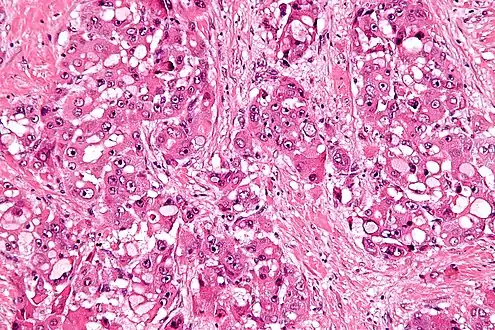

| Micrograph of fibrolamellar hepatocarcinoma showing the characteristic laminated fibrosis between the tumor cells with a low NC ratio. H&E stain. | |

The histopathology of FLC is characterized by laminated fibrous layers, interspersed between the tumor cells. Cytologically, the tumor cells have a low nuclear to cytoplasmic ratio with abundant eosinophilic cytoplasm.[1] Tumors are non-encapsulated, but well circumscribed, when compared to conventional HCC (which typically has an invasive border).

High mag.